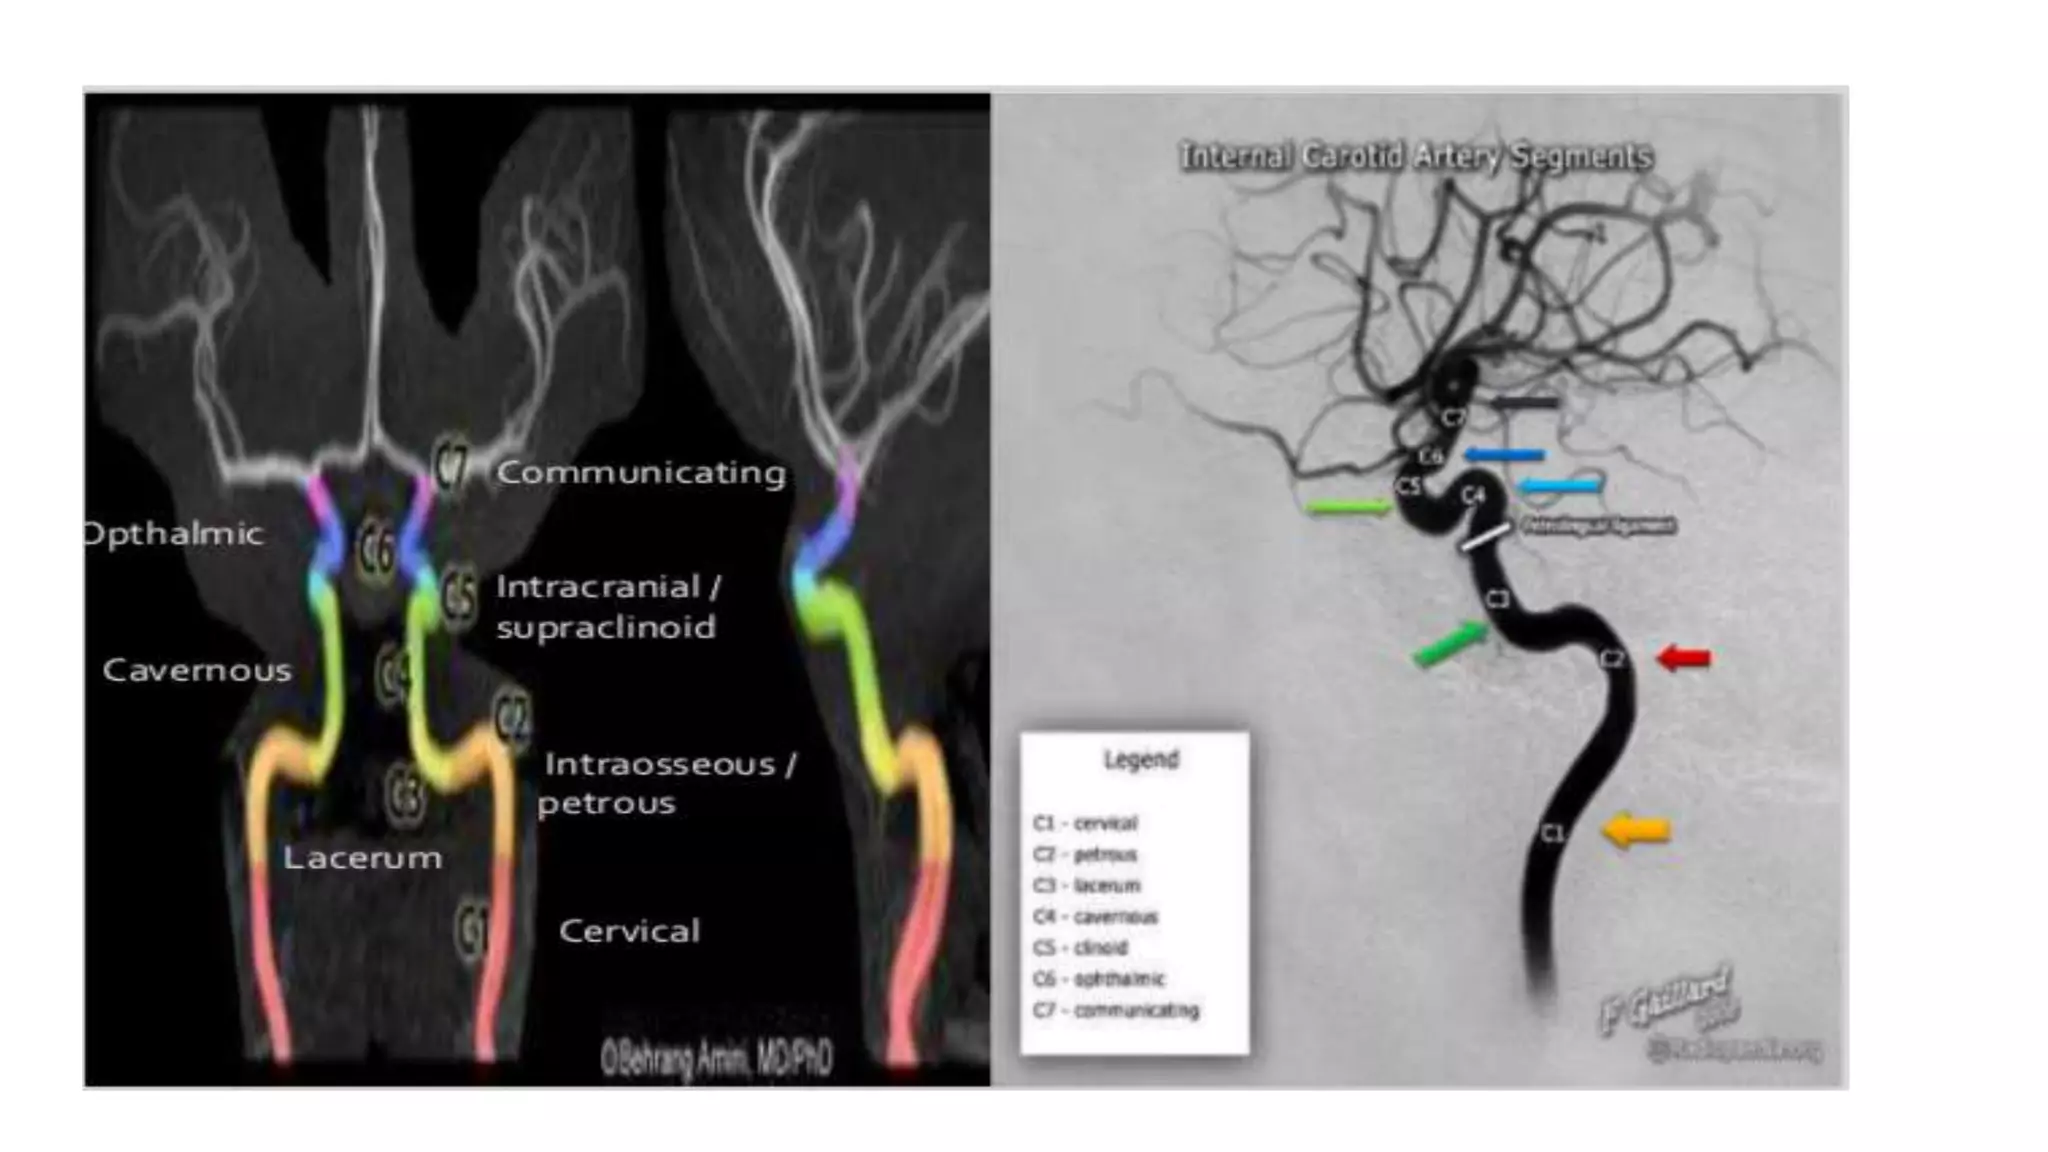

Segments of ICA

C1-Cervical segment

C2-Petrous ICA

C3-Lacerum

C4-Cavernous ICA

C5-Clinoid segment

C6-Ophthalmic segment

C7-Communicating

Segment

Segments of ICA C1-Cervicalsegment C2-Petrous ICA C3-Lacerum C4-Cavernous ICA C5-Clinoid segment C6-Ophthalmic segment C7-Communicating Segment CAROTID BULB ASCENDING SEGMENT CERVICAL ICA Lateral view